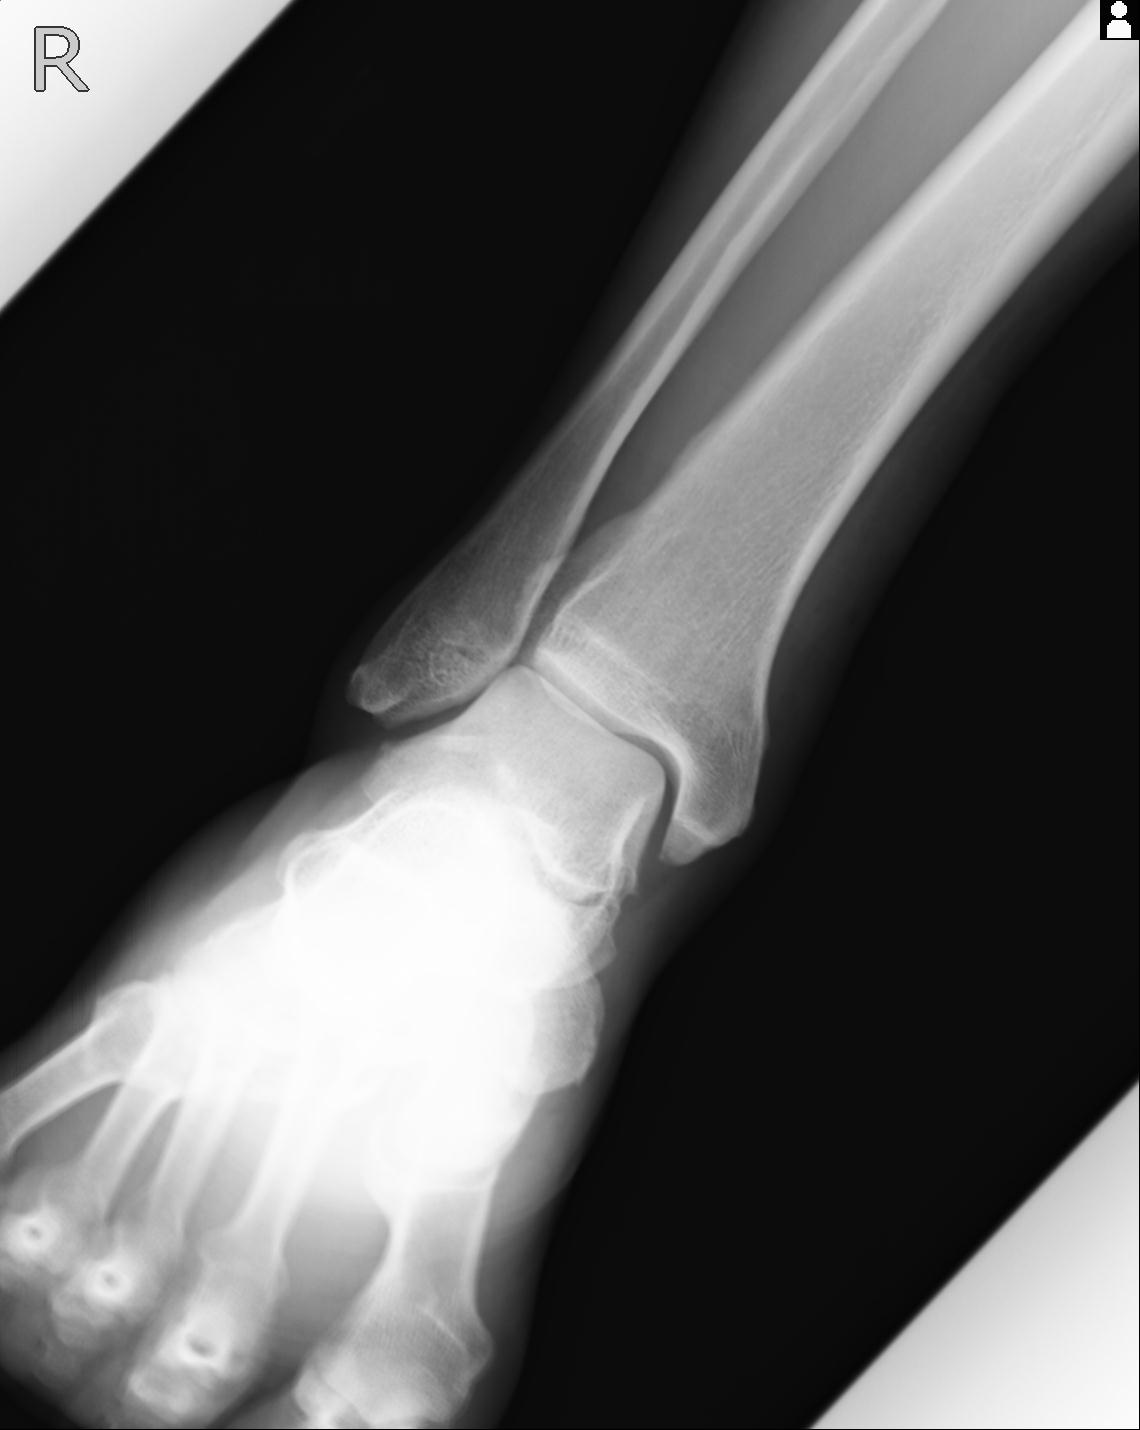

102755 1/4 2R 1/15 2R 右足関節 68歳女性 右三果脱臼骨折